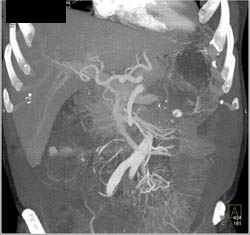

Diagnosis

Ampullary Tumor